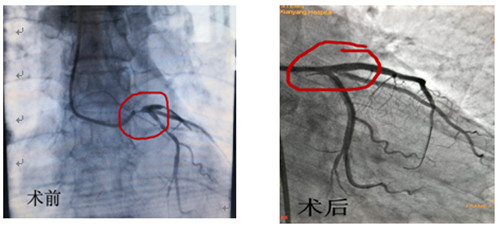

術(shù)前術(shù)后造影對(duì)比

2018年12月13日心血管病二病區(qū)收治1名外院轉(zhuǎn)來的冠心病左主干病變患者,冠狀動(dòng)脈造影顯示:左冠優(yōu)勢(shì)型,左主干自開口部至末端嚴(yán)重狹窄,狹窄程度至95%-99%,前降支近段80%-90%狹窄,回旋支近段80%-90%狹窄,右冠中段70%-80%狹窄。入院后給予充分抗血小板、抗凝治療,患者心絞痛仍頻繁發(fā)作,持續(xù)時(shí)間長,如突發(fā)急性心肌梗死、猝死風(fēng)險(xiǎn)極高。依據(jù)最新血運(yùn)重建指南,SYNTAX評(píng)分26分,在患者及家屬不同意冠狀動(dòng)脈搭橋術(shù)的情況下,選擇PCI術(shù)。左梅主任對(duì)患者進(jìn)行認(rèn)真的術(shù)前評(píng)估:對(duì)于左主干分叉部位嚴(yán)重狹窄的病例,術(shù)式的選擇、支架策略、支架選擇、邊支保護(hù)膨脹貼壁程度等手術(shù)方案對(duì)于術(shù)中風(fēng)險(xiǎn)控制、預(yù)后影響極大。由此,我們認(rèn)為IVUS(血管內(nèi)超聲)指導(dǎo)下更有利于方案的實(shí)施。

12月16日早上8點(diǎn)30分手術(shù)如期進(jìn)行,術(shù)前IVUS評(píng)估:左主干自口部至末端彌漫狹窄,最小管腔面積<1mm2,斑塊負(fù)荷程度>90%,主要為纖維脂質(zhì)斑塊,無明顯鈣化,回旋支開口尚可,前降支近段主要為纖維脂質(zhì)斑塊,亦無明顯鈣化。據(jù)此,手術(shù)方案定為:前降支近段至左主干口部串聯(lián)植入2枚支架,回旋支近段1枚支架,無需旋磨、切割,支架植入后IVUS評(píng)估:支架膨脹、貼壁良好,左主干口部支架梁覆蓋完全,手術(shù)完美收官。此系心內(nèi)二病區(qū)左梅主任及其團(tuán)隊(duì)在導(dǎo)管室配合下完成的我院首例自主IVUS指導(dǎo)下左主干PCI。